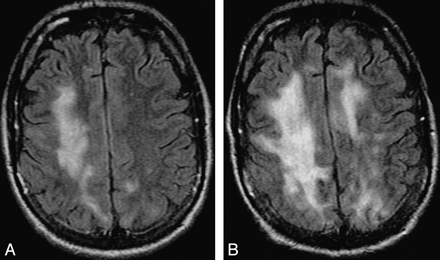

On T2-weighted sequences, lesions appear hyperintense to the cortex. Hyperintensity is seen within the lesion and also in the adjacent white matter, which is more prominent on FLAIR. On T2-weighted sequences, the demarcation of the lesion margin from the adjacent uninvolved gray matter is clearly seen (Fig 1). If PML progresses, smaller lesions coalesce, as seen in Fig 4. With progression or involution of a lesion, the central area becomes necrotic and appears hyperintense on T2 and is often attenuated on FLAIR sequences (Figs 1 and 6). In some cases, there may be microcysts at the center of an active lesion on T2-weighted sequences (Fig 5). We have seen microcysts in 6 of our 15 patients with cPML.

Progression of cPML. A and B, These FLAIR images, 4 months apart, from an HIV-positive patient with cPML demonstrate typical progression of the supratentorial white matter FLAIR hyperintensity.